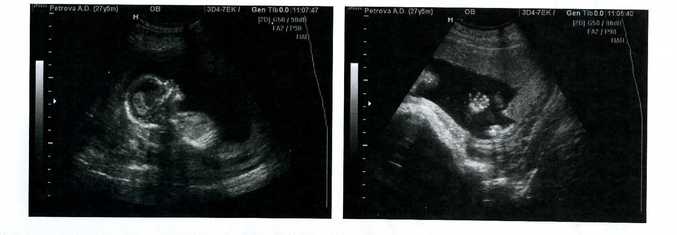

Из позитивного - живот прилично вырос. Малыш пинается уже очень сильно! Боюсь представить, что дальше будет :) В больнице делали очередное УЗИ. Сынок растёт и развивается, по словам врача, "как по учебнику". Все показатели в норме. Всё хорошо. До отпуска остается меньше 3х недель. А выйду я уже перед самым декретом. Так что работать мне осталось всего ничего. У малыша уже целый гардероб! Будет время - пофотографирую) Осталось купить коляску-кроватку. Займемся этим в конце августа.